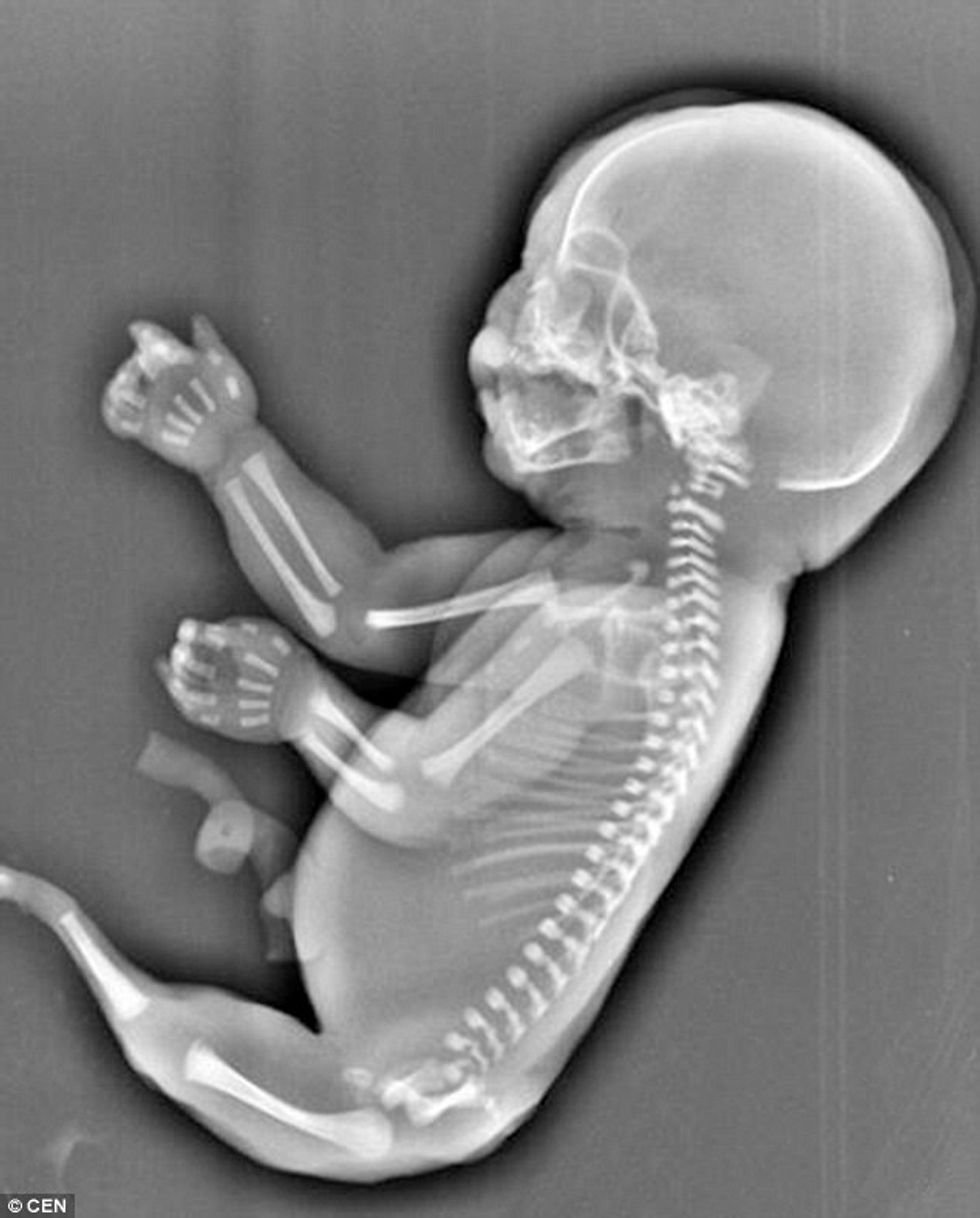

Skanimet kanë treguar se në barkun e 23-vjeçares po rritej një fetus pa këmbë, por vetëm me një bisht të gjatë.

Mësohet se fetusi vuante nga një gjendje e rrallë që quhet sironomelia, apo ‘Sindroma e Sirenës’, që i bën këmbët të jenë të kapura, duke dhënë përshtypjen se është një bisht i gjatë.